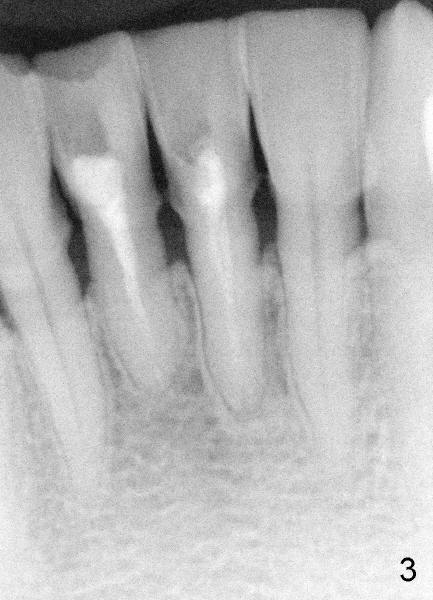

Two PAs were taken at different angulations (Fig.1,2 vs. 3,4).  The shortest M-D width of the tooth #24 is 3.16 mm (Fig.4 vs. 4.54 mm in Fig.2, probably close to the B-L width).

There is plenty of dimension in height.  What is the appropriate size of the implant?  How to handle the discrepancy of M-D and B-L widths?

Dear Dr. Borgner: Thanks for the advice again. The patient showed up this afternoon. The tooth (in fact #25 in Fig.5) is pretty badly broken down, but the patient is not ready for implant right now. Prefabricated post and temporary crown are provided. Fig.6 shows the longest post space that can be gained. The mesiodistal dimension of the tooth is 3 mm above gingiva clinically; the buccolingual 5 mm; the minimal dimension between #24 and 26 is 3.5 mm. There is plenty of height. The longest one piece tapered implant from Tatum Surgical is 17 mm. The appropriate implant should be 3x17 or 3.5 x17 if the proximal surfaces of #24,26 are to be trimmed further. This was done when the temporary crown was fabricated. Anyway, thanks for guidance.